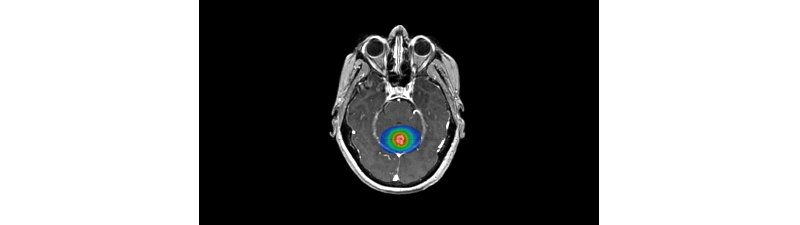

Technological advances allow surgeons to visualize exactly where the tumor is and the surgical path to it.

Treatment of brain tumors is often challenging and risky due to their complex nature and proximity to sensitive tissue. Improved visualization and planning allow for a better understanding of the tumor before surgery begins.

Fluorescence-Guided Surgery shows where the tumor is located in the brain beyond what can be seen with the naked eye.